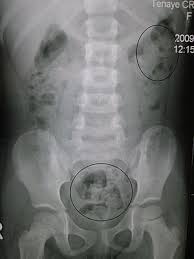

You can usually treat it at home with simple changes to your diet and lifestyle. Global issues surrounding physical activity online course: Our medical experts explain home remedies for constipation, other symptoms of constipation, how to get rid of constipation, foods that cause constipation, medicine for constipation that works, and more. Constipation is a condition in which you may have fewer than three bowel movements a week; Constipation is when it is very hard to pass stool (defecate): Obstructive constipation results from obstruction of the passage of stool. Constipation develops when stool becomes hard and difficult to pass. Ideally, you need both on a regular basis. Move through a few facts about constipation. Constipation is common and it affects people of all ages. Certain supplements can also help improve your regularity, whether you're struggling with constipation or diarrhea. If you are experiencing a new onset of constipation without any of the symptoms listed above, try to increase your fluid intake and your physical activity level. Find out what could be the cause and learn how to prevent and treat infrequent bowel movements.